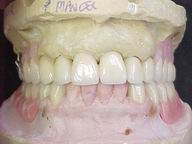

Reabilitação funcional e estética em ambas as arcadas

com próteses fixas e removíveis de encaixe de precisão.

Fase Intermediária Vista Frontal

Vista Oclusal Sobre Modelos de Gesso